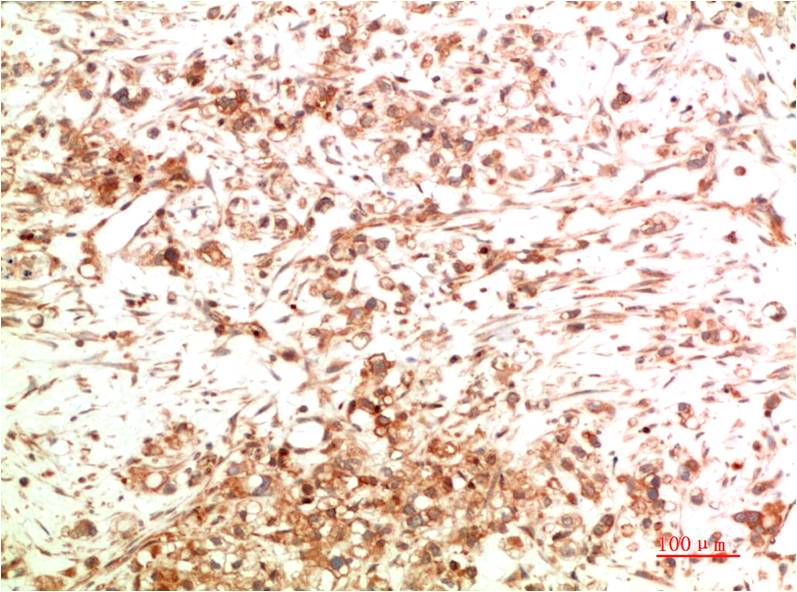

Immunohistochemical analysis of paraffin-embedded Human Ovarian Carcinoma Tissue using ATG5 Mouse mAb diluted at 1:200.

Immunohistochemical analysis of paraffin-embedded Human Breast Carcinoma Tissue using ATG5 Mouse mAb diluted at 1:200.